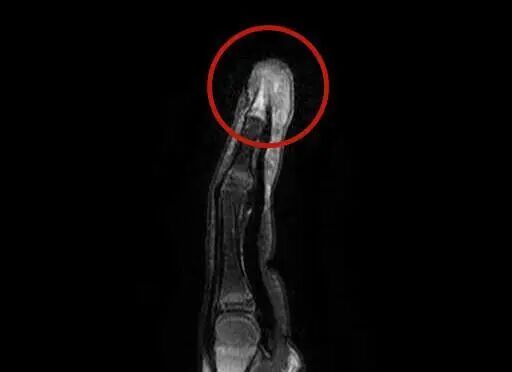

这下妈妈慌了神,连忙带小雨来到杭州市临平区妇幼保健院,小儿外科主任吴红军仔细查看了小雨的情况,结合检查结果,诊断为“脓性指头炎”,立即为小雨做了手指脓肿切开引流手术,并收住入院静脉输液抗感染治疗。而更令人揪心的是,核磁共振显示小雨的指骨已经出现了吸收破坏,这意味着感染已经侵袭到骨骼,发展为更加严重的“骨髓炎”!

放射检查:脓性指头炎/医院供图